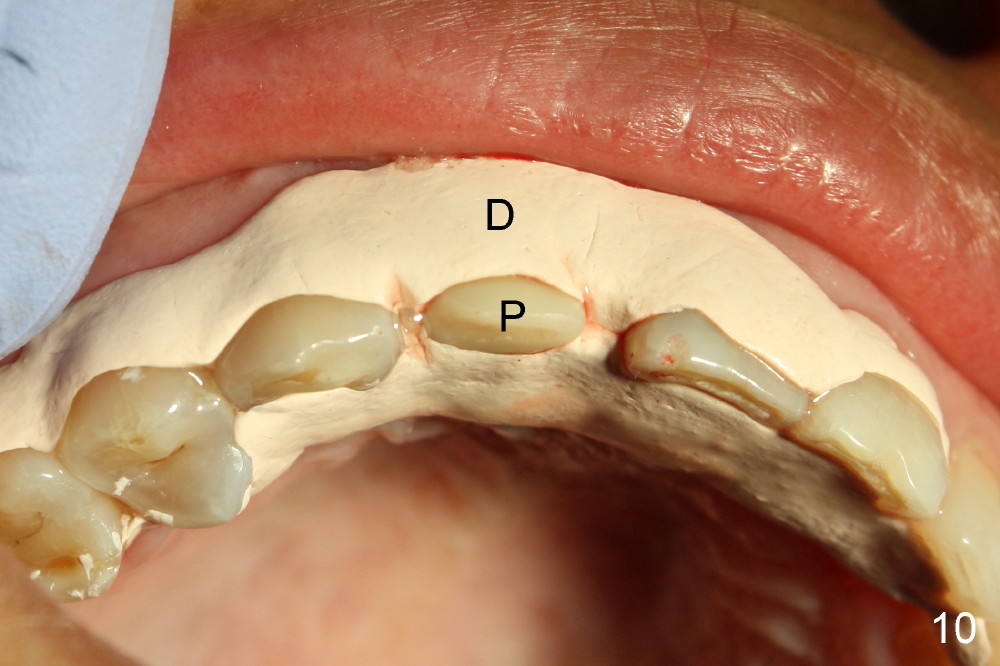

Malpositioned implant in the anterior region is cosmetically unacceptable. Immediate provisional allows us to note the issue immediately. The crown looks too long. Secondly, the provisional is easily dislodged, since the buccal aspect of the angled abutment is over trimmed (Fig.1). The implant (3.8x14 mm), which has been placed 3.5 months, is unexpectedly easily removed by reverse torque (Fig.2). The buccal wall is intact, whereas there seems to be enough bone lingually to place an implant. A small incision is made (Fig.11) so that the gingival tissue can be transferred buccally (Fig.12) and the immediate implant is to be placed palatally (Fig.13 white circle). There is no difficulty forming osteotomy in the palatal wall, followed by inserting 4.5x20 mm tap at the depth of 17 mm (Fig.3,5). But the tap is not palatal enough (Fig.4). By removing more palatal bone, the 4.5x17 implant (Fig.6) appears to be placed palatally enough for restoration (Fig.7; A: abutment; *: buccal gap). The biggest problem is that the palatal flap (Fig.7 arrowheads) cannot be pushed buccally; instead remains palatally. This leads to buccal tissue deficiency (Fig.8). Connective tissue graft is offered, but declined. The patient insists that she has low smile line. Following immediate provisional, mixture of allograft and synthetic graft is placed in the buccal gap (Fig.9). The overbuilt graft is held in place by perio dressing.